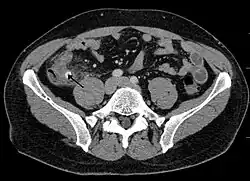

A fecalith marked by the arrow which has resulted in acute appendicitis.

A fecalith is a stone made of feces. It is a hardening of feces into lumps of varying size and may occur anywhere in the intestinal tract but is typically found in the colon. It is also called appendicolith when it occurs in the appendix and is sometimes concurrent with appendicitis.[1] They can also obstruct diverticula. It can form secondary to fecal impaction. A fecaloma is a more severe form of fecal impaction, and a hardened fecaloma may be considered a giant fecalith. The term is from the Greek líthos=stone.[2]

A small fecalith is one cause of both appendicitis and acute diverticulitis.